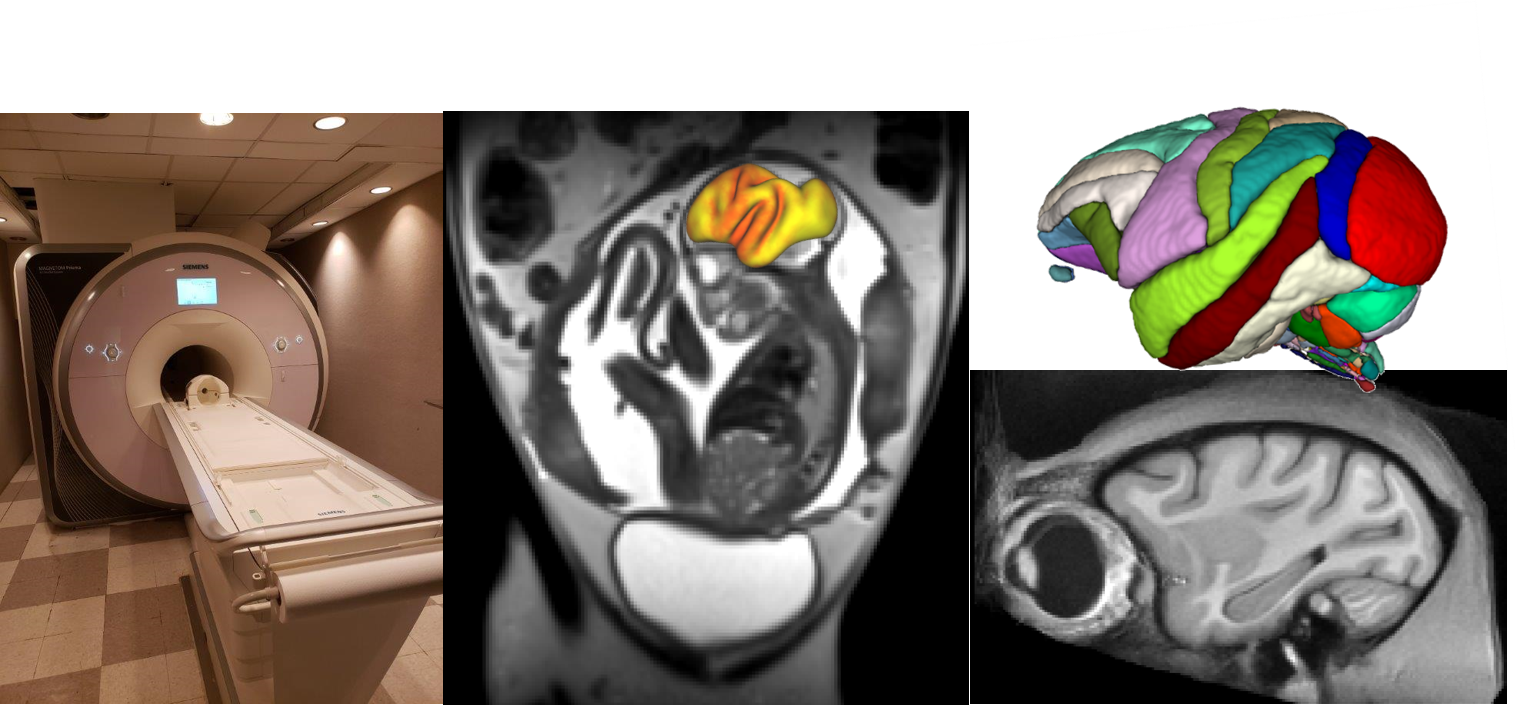

MRI scanner and examples of brain scans

The Magnetic Resonance Imaging (MRI) core provides ONPRC investigators with equipment and assistance to perform MRI exams of NHP subjects.  As a satellite facility of the OHSU Advanced Imaging Research Center (AIRC), infrastructure and technical support exist to customize MRI investigations so that researchers can take advantage of the close similarity between human and NHP anatomy and physiology to develop new MRI research and diagnosis techniques and applications.

The ONPRC MRI building is a 2500 sq. ft. facility, housing a Siemens Magnetom 3 T whole-body MR instrument.  In the winter of 2017, the MRI system was upgraded with Prisma fit 4G technology.  A wide variety of radiofrequency coils are available to support a diverse array of applications. A 16-channel pediatric head coil fits both juvenile and adult rhesus macaque heads.  A custom-built 16-channel receive array is also available for studies focused on cerebral cortex. This coil is interfaced with a stereotaxic head positioning frame for the presentation of visual stimuli. Abdominal and fetal imaging is performed using a 15-channel "extremity" coil. Small and large flexible coils are also available that can be shaped to match the contour of the thorax or abdomen of the subjects.